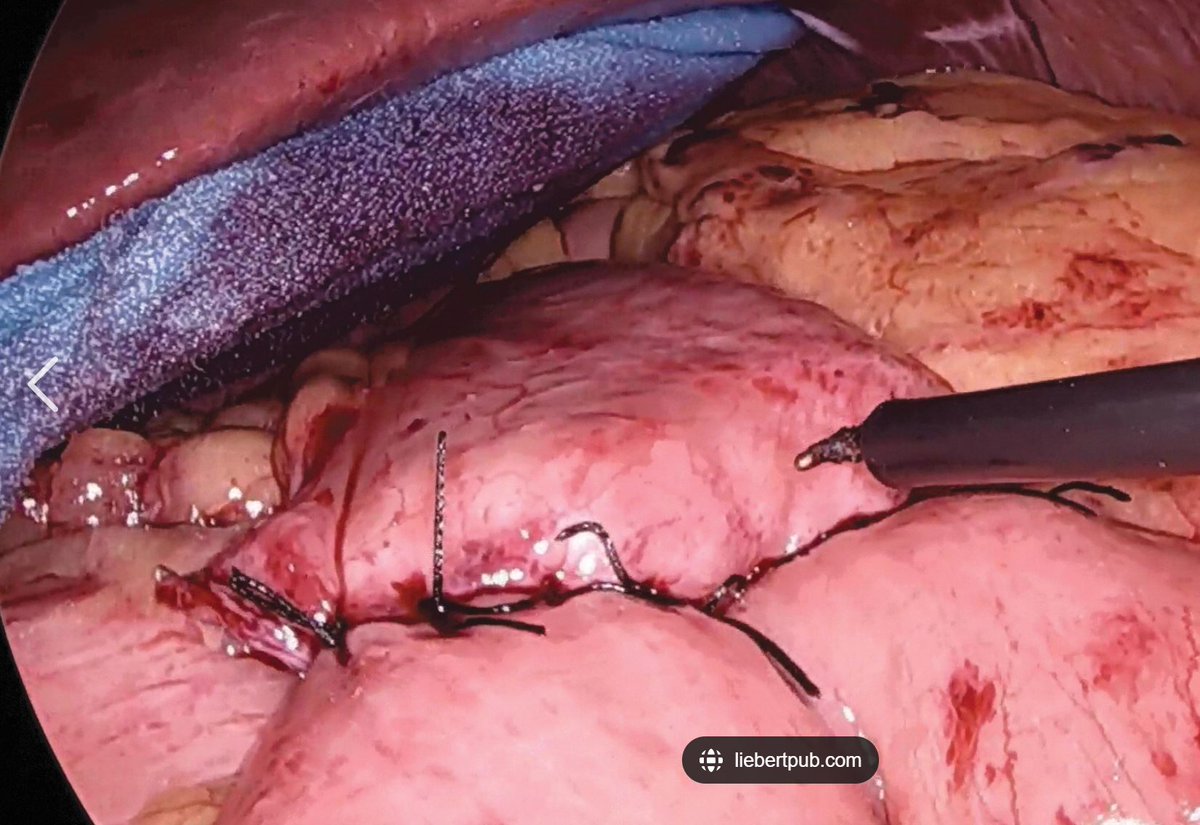

3-0 silk "popoffs" are often used to do Lembert sutures on the outer layer of a bowel anastomosis.